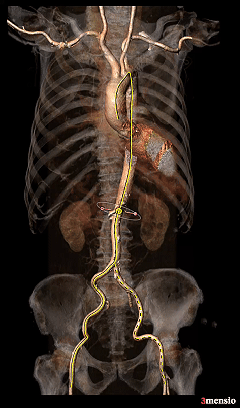

术前CT分析

Annulus

25.8mm

LVOT

瓣环水平夹角

52°

STJ 27.0mm

高21.0mm

AAO

31.6mm

L-29.9mm

R-30.0mm

N-31.6mm

-

三叶瓣,瓣叶增厚并钙化

直筒型LVOT,窦部空间不大

水平夹角52°,非横位心

瓣上 2mm

24.7mm

瓣上 4mm

25.5mm

瓣上 6mm

瓣上 8mm

24.0mm

瓣上 10mm

23.3mm

瓣上 12mm

22.3mm

瓣叶可见明显增厚及钙化分布

可见RN侧高位轻微融合

Left Coronary

12.1mm

LCA & Leaflet

12.7mm<15.8mm

Right Coronary

17.1mm

RCA & Leaflet

16.3mm<19.4mm

双侧冠脉开口高度可

左、右冠瓣叶长度>冠脉开口下缘到根部距离

结合SOV、STJ测量,窦部空间较小,预估冠脉阻挡风险较高

收缩期测量心室腔稍大

心室壁厚度尚可

钙化积分测量达1546mm3

极重度钙化,左窦、无窦钙化较重

外周入路条件可